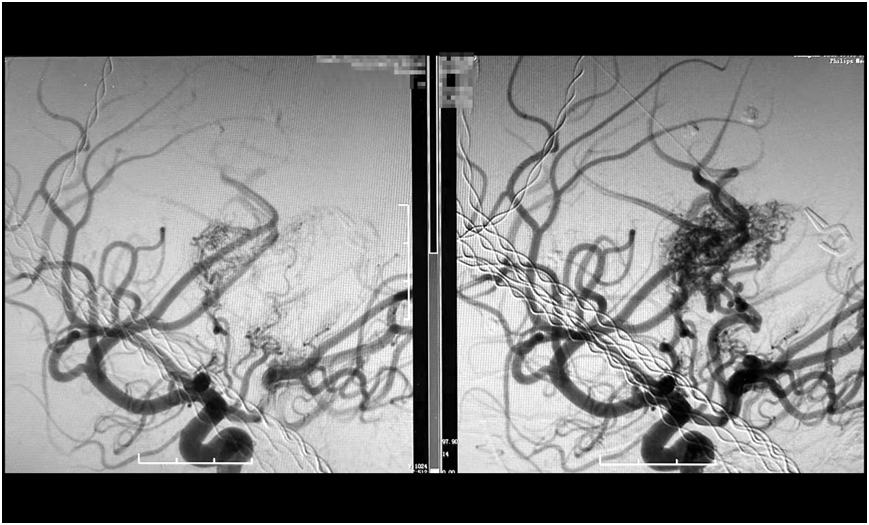

經過數小時的精雕細琢,手術團隊成功栓塞預期目標責任血管。術后造影顯示,假性動脈瘤已完全消失,畸形血管團達到預期栓塞效果,所有正常血管血流保持通暢(mTICI 3級)。

巨大腦動靜脈畸形(右),被順利栓塞(左)